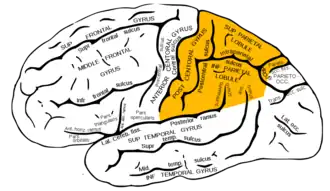

Lateral surface of left cerebral hemisphere, viewed from the side. (Parietal lobe is shown in orange.) | |